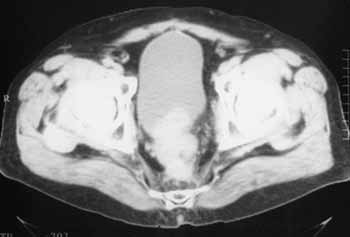

Рис. 4. Рецидив. Выбухание рецидивных масс в просвет мочевого пузыря.